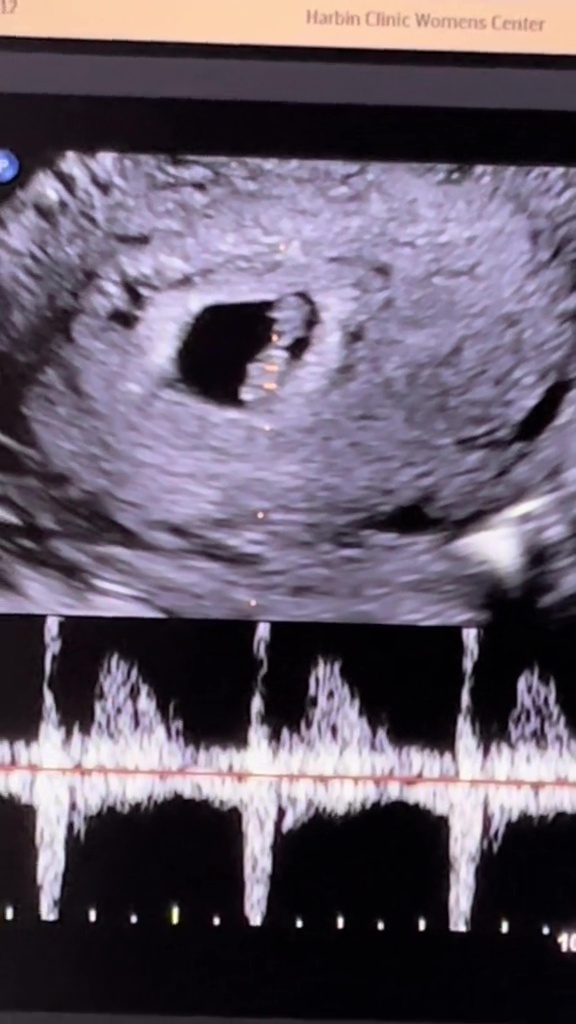

The internet went wild after the pair gained a huge fan following. And now that they are expecting images of an ultrasound shown as proof, fans are crying and scratching their heads over how something like this could even be possible in the first place.

In a video that was shared across the TikTok app, 63-year-old Cheryl explained how she just found out nearly one week back that she was all set for motherhood again. It was a miracle and even doctors were skeptical at first but it was later revealed how they had opted for surrogacy and therefore the surrogate was pregnant.

The pair shared their first experience of hearing the baby’s heartbeat and it was just so memorable for them. They cannot wait to see what the future holds and